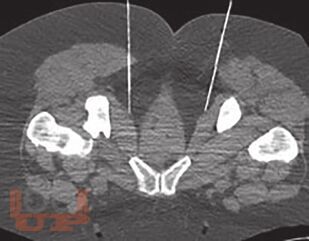

В учебном пособии отражены современные взгляды на одну из актуальных медицинских проблем - невропатию половых нервов. Авторами даны определение и классификация заболевания. Подробно рассмотрены мультидисциплинарные аспекты его патогенеза, диагностики и лечения. Представлены собственные результаты применения малоинвазивных хирургических методов лечения пациентов с невропатией половых нервов.